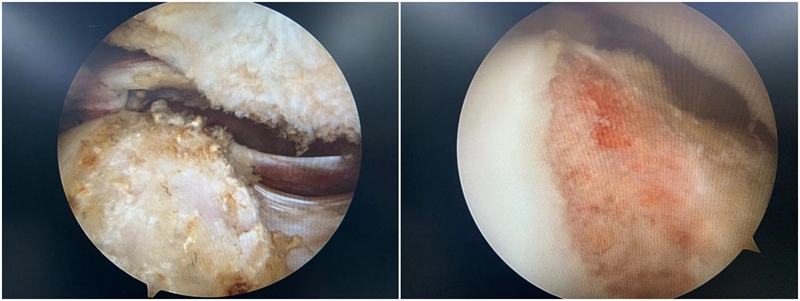

家庭不幸,首先受到伤害的就是孩子。处在髋关节这个小家庭中的盂唇也是如此。髋关节盂唇是附着于髋臼边缘的一层软组织结构,盂唇本身是有由大量的环形纤维组成,其形态与外观和膝关节的半月板类似。除了外形上,髋关节盂唇在功能上也与半月板有几分相似:首先可以增加髋臼的表面积和体积,起到加深覆盖的作用,这样髋关节可变得更加稳定;其次可以为髋关节提供负压,类似于保温杯上的“密封圈”,有了髋关节盂唇的覆盖,可以保持髋关节内的负压吸引,并保持髋关节液留在关节腔内,从而发挥其滋养髋关节表面软骨,均衡关节内应力的作用;最后,盂唇在维持关节液的平衡方面也有着重要的作用。因为处在髋臼和股骨头的中间,而且比较脆弱,当存在髋关节撞击的时候,一般首先损伤的就是盂唇。盂唇损伤在髋关节撞击综合征的患者中非常常见。

图4 髋关节镜术中图片,可见明显盂唇撕裂伴充血

图9 Cam型撞击,通过磨钻磨除

2.盂唇损伤的治疗:盂唇损伤广泛存在于髋关节撞击综合征中。对于存在修复条件的盂唇损伤,目前推荐行盂唇修复术;而对于盂唇严重磨损无法修复或横断的情况,则可考虑行盂唇清理、盂唇部分修复或盂唇重建术。手术原则是对损伤的髋臼盂唇尽量予以缝合修复,恢复髋臼盂唇的解剖结构,从而恢复髋臼盂唇的功能,避免由于髋臼盂唇缺损造成的髋关节退变。

图10 髋关节盂唇损伤及修复